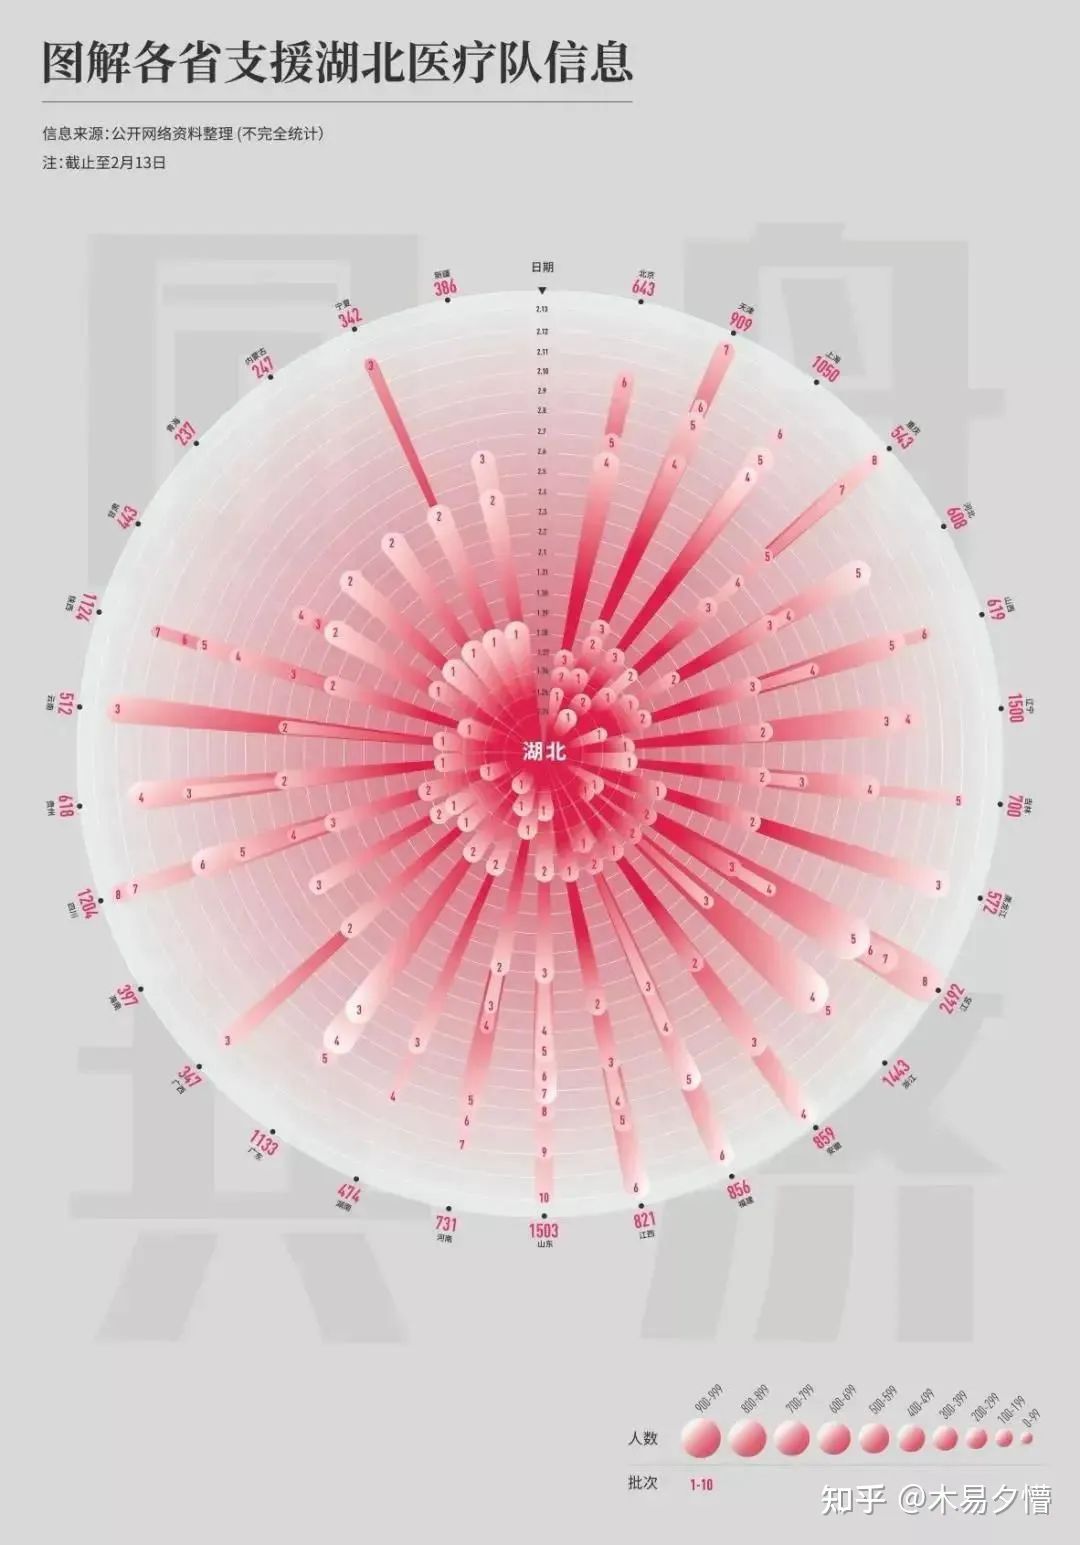

《同舟共济-图解各省支援湖北医疗队信息》

作者:张兴宇 | 南京艺术学院设计学院

设计说明:面对疫情,全国的医务工作者义无反顾地奔赴灾区。一方有难,八方支援,紧要关头,总有人站出来,向所有逆行者致敬!